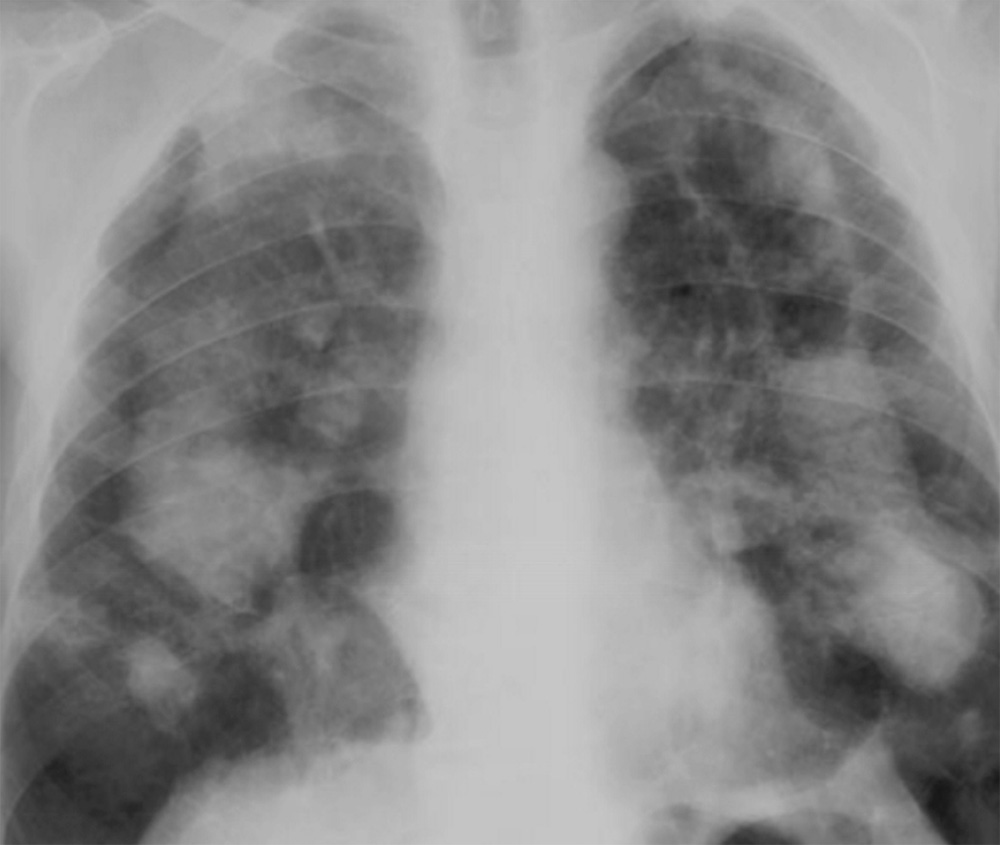

Рисунок 4. Силикоз. Определяются диффузные двусторонние интерстициальные изменения – распространенный пневмосклероз